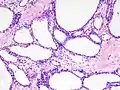

Diagram by Mikael Häggström, M.D.